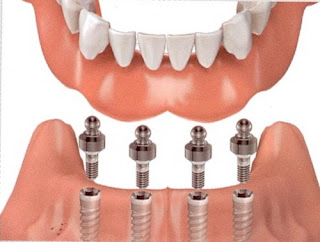

Implant được coi là phương pháp tiên tiến nhất hiện nay, được cho là thành tựu vĩ đại nhất trong lĩnh vực nha khoa, được giới chuyên gia đánh giá cao, bởi đây là phương pháp có nhiều ưu điểm nhất, trước kia khi mất răng các bạn không muốn mài răng để phục hình răng miệng thì có thể nó làm răng sứ là phương pháp tốt nhất, ngày nay với phương implant ra đời không chỉ khắc phục được những khuyết điểm của phương pháp phục hình răng truyền thống mà con có những ưu điểm vướt trội, việt răng implant được cấy trực tiếp vào xương hàm không làm ảnh hưởng gì đến răng thật, độ bền chắc, độ cứng cáp được đánh giá không thua kém gì so với răng thật giúp các bạn thoải mái trong giao tiếp ăn uống và phương pháp này tồn tại vĩnh viễn.

Implant được coi là phương pháp tiên tiến nhất hiện nay, được cho là thành tựu vĩ đại nhất trong lĩnh vực nha khoa, được giới chuyên gia đánh giá cao, bởi đây là phương pháp có nhiều ưu điểm nhất, trước kia khi mất răng các bạn không muốn mài răng để phục hình răng miệng thì có thể nó làm răng sứ là phương pháp tốt nhất, ngày nay với phương implant ra đời không chỉ khắc phục được những khuyết điểm của phương pháp phục hình răng truyền thống mà con có những ưu điểm vướt trội, việt răng implant được cấy trực tiếp vào xương hàm không làm ảnh hưởng gì đến răng thật, độ bền chắc, độ cứng cáp được đánh giá không thua kém gì so với răng thật giúp các bạn thoải mái trong giao tiếp ăn uống và phương pháp này tồn tại vĩnh viễn.